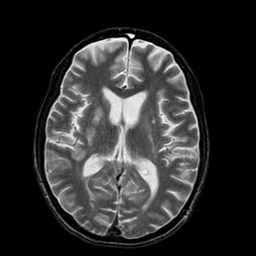

In this paper, we propose a bidirectional learning model, known as dual contrast cycleGAN (DC-cycleGAN), for medical image synthesis from unpaired data. Specifically, a dual contrast (DC) loss is formulated that leverages the advantage of samples from the source domain as negative samples to indirectly build constraints between real source and synthetic images via discriminators, and synthesize images more related to the target domain by enforcing the synthetic images to fall far away from the source domain. In addition, structural similarity index (SSIM) [35] and cross-entropy (CE) [48] are integrated into the DC-cycleGAN structure to avoid disappearing gradient information that is caused by a mean absolute error (MAE) and synthesizing irrelevant images. SSIM considers luminance [35] and CE converges fast as its back-propagation error is less than MSE [28]. As can be seen in Figs. 1 and 2, using SSIM and CE with dual contrast can generate more clear and accurate MR images as compared with that of MAE and MSE, and SSIM and CE without dual contrast loss. Although both SSIM and CE with dual contrast and without dual contrast generate similar CT images, SSIM and CE with dual contrast quantitatively generate better images as shown in Table 4. The experimental results indicate that DC-cycleGAN is able to consider more complex features such as structure in synthesizing images and produce remarkable results as compared with other state-of-the-art methods reported in the literature.

Tables 3 and 4 show the results of MR and CT synthesis, respectively. As can be seen, all components play vital role in both tables. SSIM & CE (w) performs significantly better than other losses in synthesizing MR images. This also can be seen visually in Fig. 1. In contrast, SSIM&CE (w) performs slightly better than SSIM&CE (wo) in synthesizing CT images, both generate more or less similar CT images (see Table 4).